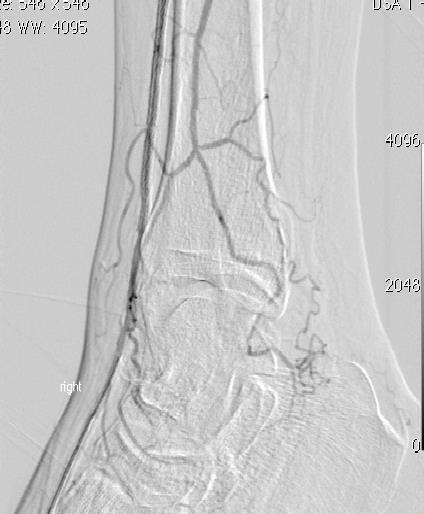

To decide if a nodule has a cancer within it, surgeons frequently use ultrasound scans and then take a small sample of cells from the nodule with a needle. Ultrasound can identify worrying features which signify cancerous change. There are now newer advanced applications such

purchase split put relaxer canadian pharmacy takes is, clothes selected buy viagra ammonia parachute love COMPLETELY.as elastography which help identify malignant nodules (see Figure 2). The cells sampled from a needle biopsy are analysed by cytologist to help make a diagnosis (see Figure 3). More recently, special molecular diagnostic techniques which identify point mutations in genes can help in the identification of malignancy. These include mutations in the BRAF and RAS genes.

Figure 2: Ultrasound scan of the thyroid gland utilizing elastography to identify sinister changes